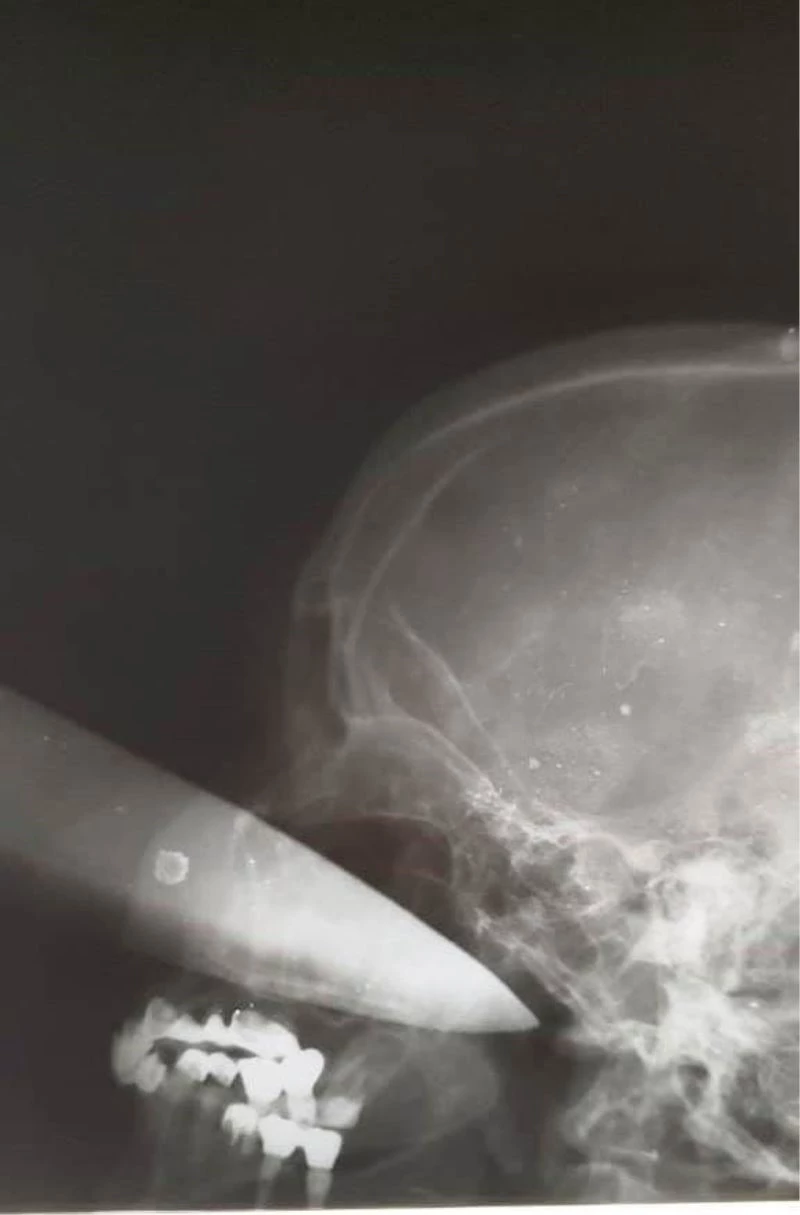

Rusya’da sarhoş koca tartıştığı sırada eşinin gözüne büyük bir bıçak sapladı. Hastaneye kaldırılan kadının gözünü kaybettiği belirtildi.

Rusya’nın Krasnodar kentinde evli bir çift arasında tartışma çıktı. Sarhoş olduğu öğrenilen koca, tartışmanın dozu artınca mutfağa gidip çekmeceden büyük bir bıçak aldı. 60 yaşındaki eşi Larisa’nın üzerine yürüyen sarhoş adam karısının gözüne bıçak sapladı. Komşuları tarafından çığlıkların duyulması üzerine olay yerine polis ve ambulans çağırıldı. Saldırgan koca polisler tarafından karakola götürüldü. Gözüne bıçak saplanan ve kanlar içinde kalan kadın ise hastaneye kaldırıldı.

Bilinci yerinde olan kadın ameliyata alındı. Doktorların uzun süren çabasıyla kadının gözüne saplanan bıçak çıkarıldı. Bıçağın kadının gözünden 25 santimetre içeri girdiği belirtildi. Talihsiz kadın bıçağın saplandığı gözünü kaybetti.